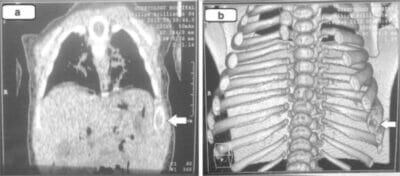

- Pulmón: en algunos pacientes que son asintomáticos, el diagnóstico se realiza accidentalmente al encontrar nódulos pulmonares en la radiografía de tórax. En otros casos se observa, tos crónica y disnea.

El diagnóstico se realiza por confirmación histológica a través de una biopsia tisular. La tinción de hematoxilina-eosina de la biopsia mostrará algunas características de las células de Langerhans como por ejemplo, gránulos plasmáticos rosados y margen celular distintivo. La presencia de gránulos de Birbeck en la microscopía electrónica y las características inmunohistoquímicas como por ejemplo la positividad para CD1, resultan pruebas más específicas. Algunos exámenes de laboratorio de rutina como el hemograma, perfil hepático, y otras pruebas sirven para orientar el diagnóstico (principalmente para descartar otras posibles causas). Los exámenes imagenológicos mostrarán lesiones osteolíticas y daño pulmonar. Esto último se puede evidenciar en la radiografía de tórax al mostrar lesiones micronodulares e infiltrados pulmonares en las zonas bajas y medias. La resonancia nuclear magnética o la tomografía axial computarizada puede mostrar infiltración a nivel de la silla turca. La medición del eje endocrino y la biopsia de la médula ósea también pueden resultar útiles para el diagnóstico.